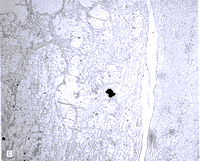

正常眼压性青光眼视网膜连续切片苏木精-伊红染色发现视网膜节细胞及其轴突与对照眼相比有显著丢失。另外,内核层的厚度(3~4层细胞)与对照眼相比(8~9层细胞)明显减少(图5A)。视网膜切片检查偶见视网膜细胞核或胞浆浓缩、核固缩、或有凋亡小体。TUNEL技术所显示的强荧光染色的核代表DNA碎片及核染色质浓缩(图5,B和C)。TUNEL阳性细胞在视网膜节细胞层最多见;但也有一些细胞见于内、外核层。TUNEL阳性节细胞散在分布,约占每一切片的全部节细胞的0.1%。年龄相匹配的正常对照眼中未见TUNEL阳性细胞。

图5 正常眼压性青光眼细胞凋亡的证据。A,正常眼压性青光眼视网膜中周部节细胞及其轴突丢失。箭头所示为一个核固缩胞浆完整的节细胞;箭状物所指为一个有浓缩核和收缩的胞浆的节细胞(苏木精-伊红染色;原大×100)。B,正常眼压性青光眼患者眼切片中节细胞和视网膜内核层中用终端脱氧核苷酸转移酶介导的三磷酸脱氧尿核苷末端标记技术标记的阳性细胞(原大×40)。C,视网膜节细胞层TUNEL技术标记阳性细胞(箭头)(原大×100)